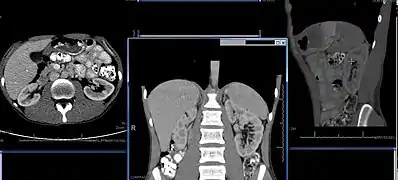

سیتی اسکن شکم که موقعیت کلیهها را نشان میدهد. تصویر چپ: قسمت فوقانی شکم، کبد را در سمت چپ (سمت راست بدن) نشان میدهد. تصویر مرکزی: در اینجا، کلیهها پایین کبد و طحال قرار دارند. تصویر راست: یک مقطع عرضی دیگر از کلیه سمت چپ.